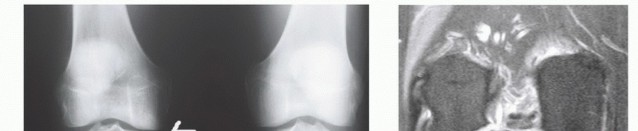

Remove soft tissue from the meniscus (capsular tissue) ( TECHFIG 1A ).

TECH FIG 1 • Lateral meniscus graft preparation. A. Meniscus following soft tissue removal and prior to bone work. B,C. Preparing bone bridge between meniscus horns on dovetail workstation.

Commercially available meniscus workstations can facilitate the bone bridge preparation into various shapes that will match tibial recipient sites (

TECH FIG 1B,C

).

The most common bone preparation techniques include dovetail, slot, and keyhole configurations ( TECH FIG 1D ).

Prepare the bone bridge shape between the meniscus insertion sites using the appropriate workstation ( TECH FIG 1E ).

TECH FIG 1 •

(continued)

D. Common bone bridge shapes. E. Ensuring bone bridge slides easily within dovetail sizing device. F. Final lateral meniscus graft (dovetail shape) with passage suture. During bone preparation, be careful not to injure the meniscal insertion sites.

Mark the superior surface of the meniscus and the popliteal hiatus with a surgical marker.

Using 10-inch flexible meniscal repair needles, place a vertical mattress suture (may place more than one if desired) through the posterior horn of the meniscus adjacent to the popliteus hiatus (

TECH FIG 1F

). Do not cut off the needles. This will serve as a passage suture to assist in the delivery and reduction of the meniscus. It can be used for fixation as well.